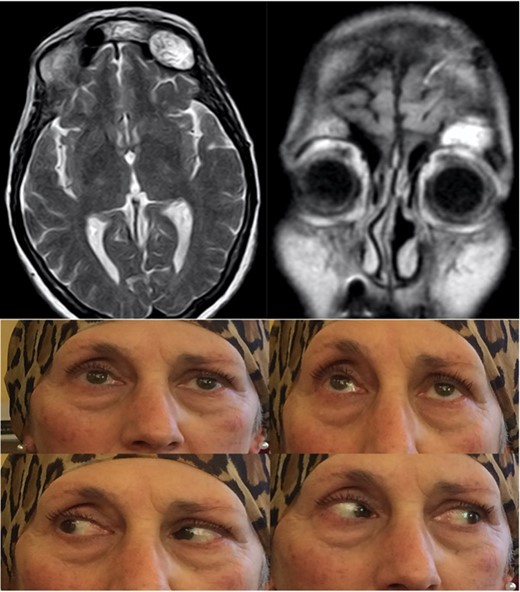

A 65-year-old female attended to our observation describing a 4-week history of left exophthalmos, which had worsened in the previous days with the association of ptosis, ophthalmoplegia and diplopia. She had no history of head trauma or previous naso-sinusal surgery. A MRI and a CT of the skull revealed a hyperintense lesion on T2-weighted images occupying the left frontal sinus that partially eroded the orbital roof and the frontal posterior wall of the sinus, with invasion of the left orbit and displacement of the ocular globe and intracranial extension without dural infiltration (Fig. 1).

Pre-operative T2-weighted MRi showing a frontal sinus mucocele with intraorbital and intracranial extension, causing ptosis, exophtalmus and diplopia.

In the post-operative period the patient underwent a standard antibiotic prophylaxis (ceftriaxone 1 g × 2/die IV) for the successive 4 days and was discharged after 5 days with no neurological or systemic complication. The histological examination confirmed the intraoperative diagnosis of mucocele, and 1 month after the procedure, the patient showed a good improvement of the exophthalmos and ophthalmoplegia with a radiological evidence of complete sinus obliteration (Fig. 3).

Post-operative T2-weighted MRi showing the fat tissue filling the surgical cavity, with improvement of the ptosis and absence of diplopia.